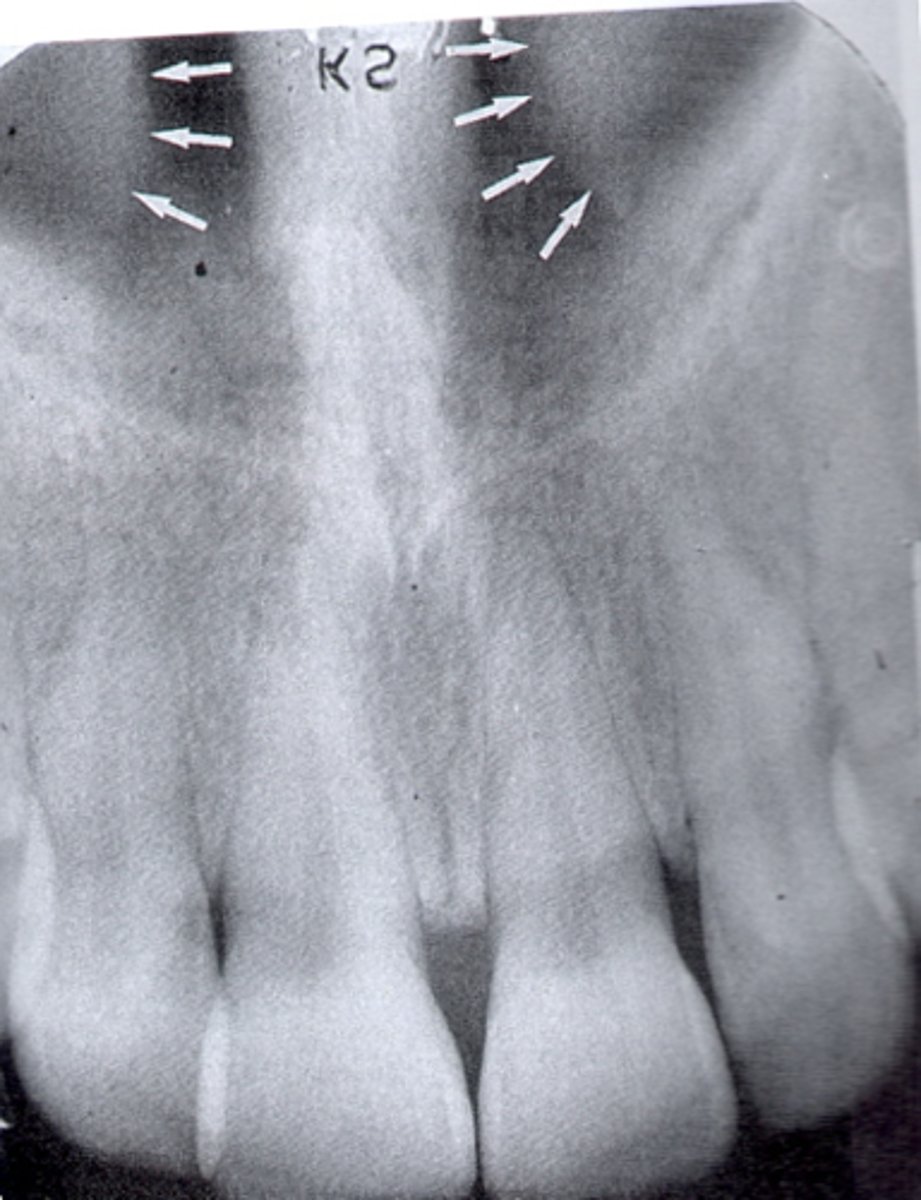

Median palatal suture

What is the radiolucent structure seen here?